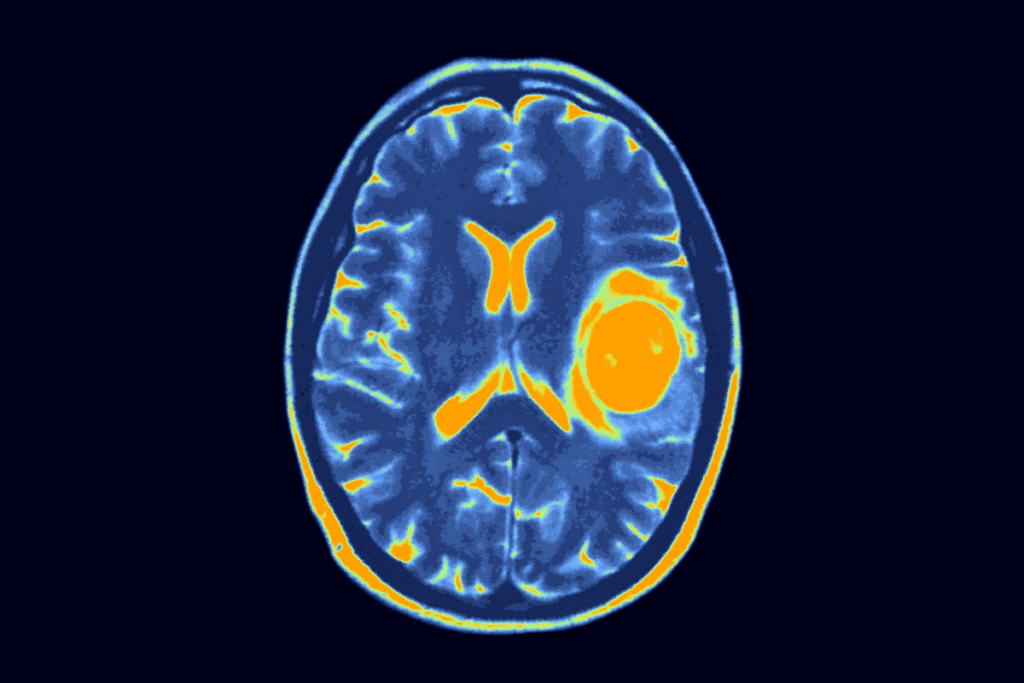

Imaging Studies

Imaging is key in finding Wilms tumor. Ultrasound is often first because it’s safe and shows solid or cystic masses. Then, CT scans or MRI give more details about the tumor and nearby areas.

Choosing between CT and MRI depends on the case. MRI is great for looking at the blood vessels and avoiding radiation. It’s also good for checking the inferior vena cava for tumor thrombus.